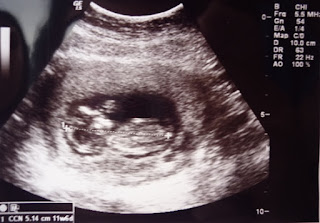

Resultado da Translucência Nucal. Foto do meu nenem!!!! \(^_^)/

Ela me orientou em tudo, inclusive conseguiu para mim o adiantamento do exame de Tranlucência Nucal. Meu GO havia pedido o exame para apos o dia 20, porém realizei hoje 16/03/2012. Na verdade eu não estava me aguentando de curiosidade, PRECISAVA ver meu bebê, ter a certeza que esta tudo bem com ele(a)!!!!

Quando vi as primeiras imagens, foi algo mágico!

Vi certinho a cabecinha do nenem, o corpinho, os bracinhos, as perninhas...

Ele(a) estava com a mao no rosto,segundo o médico provavelmente o nenem estava chupando dedo!kkkkkkkk (igualzinho a mamãe aki rsrsrs).

Mas oque me deixou sem palavras foi quando vi que ele(a) estava de pernas cruzadas...Como se estivesse sentado beeeem relaxado chupando dedo!kkkkkkkkkkkk

O medico ainda brincou dizendo que ele(a) estava "fazendo pose",hahaha nessa hora eu ja chorando, acabei misturando o choro com o riso!!!!hahahahahaha

Ouvi finalmente o seu coraçãozinho...Mais parecia um galope de cavalo, de tao rapido!!!!

O resultado da translucência Nucal não poderia ter sido melhor!

Abaixo vai fotinhas do exame e do nenem!

Vovó, eu ja tenho 51 mm \(^_^)/